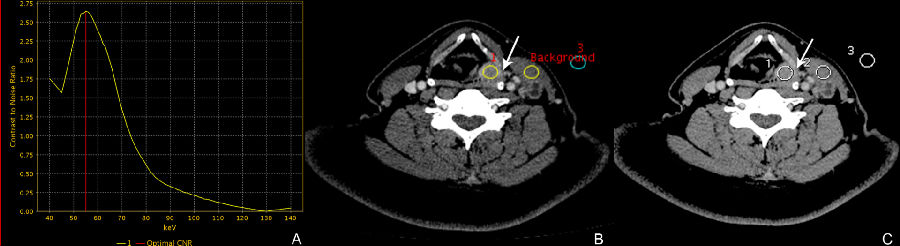

图1:58岁男性,下咽癌患者, 最佳CNR单能量55kev是病变显示的最佳Kev

小结: 我们知道,常规CT检查图像,是由混合在一起的不同能量X射线作用于人体得到的混合能量图像。因此,会有导致伪影、CT值不稳定准确及无法体现不同能量X射线影像学的特征等等弊端! 能谱CT所独有的四大工具之一的单能量工具可以获取从40Kev到140Kev之间不同X射线能量的单能图像,从而根据临床诊断不同需要选取最理想最合适的单能图像。 能谱CT四大工具中的的能谱曲线则可以反映感兴趣区(ROI)在不同keV下CT值的变化规律,显示从40到140Kev的单能量范围内的CT值的平均值和标准差,从而反映出感兴趣区组织的病变特点和规律,为临床提供可靠的诊断依据。